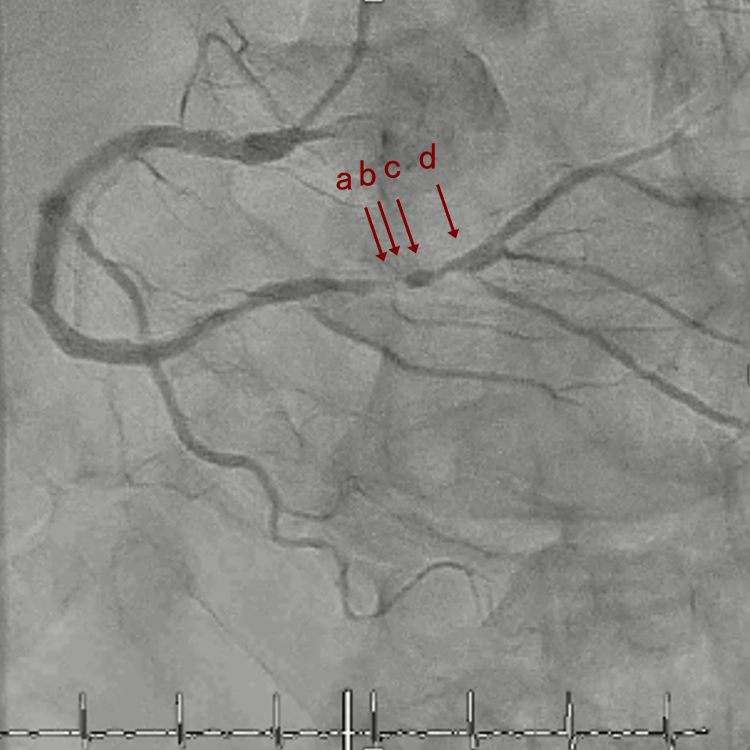

CAG

RCA distalの高度石灰化狭窄病変

OAS low speedによる引きを赤線の区間行う方針とした。

OAS low3回 造影上の切削区間の確認

末梢病変であるがOASはGlide Assistで容易にdeliveryできた